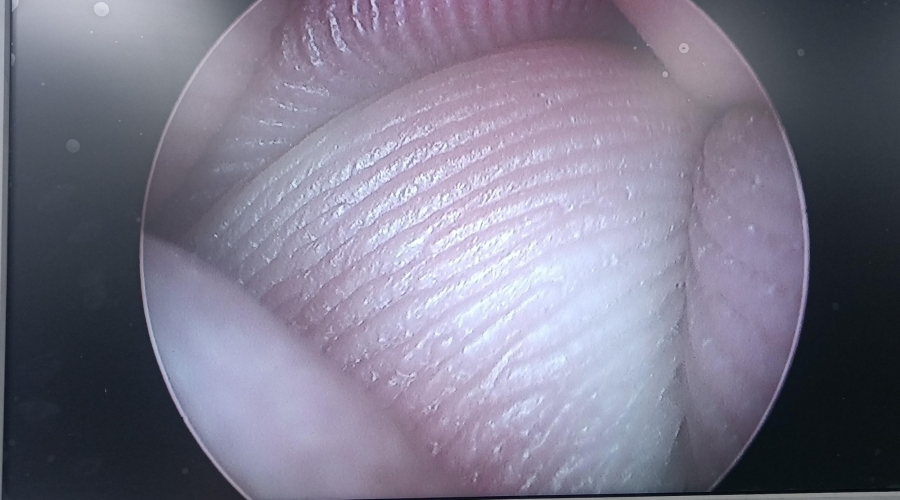

設(shè)備型號(hào)Wolf狼牌電切鏡8650.414

故障內(nèi)容圖像模糊,棒透鏡破碎,導(dǎo)光錐破碎,目鏡罩破碎,鏡身有磕碰,但不影響使用。

維修方案更換棒透鏡、導(dǎo)光錐、目鏡罩,校對(duì)圖像,內(nèi)窺鏡抗震蕩抗沖擊性能測試,內(nèi)窺鏡密封性性能檢測;內(nèi)窺鏡抗震蕩性能測試,內(nèi)窺鏡冷熱沖擊性能檢測。